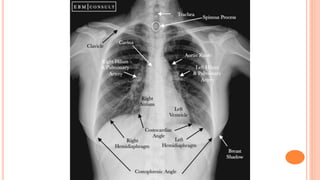

Mnemonic Explanation Note

A Airways

The trachea should be central or slightly to the right. If it is deviated, check whether it is due

to the patient's position or another pathological cause.

B Bones and soft tissues

Assess the bones visible in the image from top to bottom. The edges of the bones

should be smooth, otherwise a fracture may be indicated. Also assess for bone

density, oedema or metastatic lesion.

C Cardiac

On a PA image, the heart's width should be less than 50% of the chest width. On an AP image,

it should be between 50-60% of the chest width.

D Diaphragm

The right diaphragm is normally higher than the left. The costophrenic and cardiophrenic angles

should be clearly visible. The blunting of those angles may indicate effusion.

E Edges of the Heart The edges of the heart should be clearly defined. Otherwise, there may be

consolidation in the adjacent lung lobes.

F Fields and Fissure Check for any absence of normal lung markings in both fields. Also check for

opaque masses, consolidation, or fluid.

G Great Vessels or Assess the aorta and pulmonary vessels. The aortic knob should be visible.

Gastric bubbles A normal gastric bubble can be seen below the left diaphragm.

Mnemonic Explanation Note AAirways The trachea should be central or slightly to the right. If it is deviated, check whether it is due to the patient's position or another pathological cause. B Bones and soft tissues Assess the bones visible in the image from top to bottom. The edges of the bones should be smooth, otherwise a fracture may be indicated. Also assess for bone density, oedema or metastatic lesion. C Cardiac On a PA image, the heart's width should be less than 50% of the chest width. On an AP image, it should be between 50-60% of the chest width. D Diaphragm The right diaphragm is normally higher than the left. The costophrenic and cardiophrenic angles should be clearly visible. The blunting of those angles may indicate effusion. E Edges of the Heart The edges of the heart should be clearly defined. Otherwise, there may be consolidation in the adjacent lung lobes. F Fields and Fissure Check for any absence of normal lung markings in both fields. Also check for opaque masses, consolidation, or fluid. G Great Vessels or Assess the aorta and pulmonary vessels. The aortic knob should be visible. Gastric bubbles A normal gastric bubble can be seen below the left diaphragm.